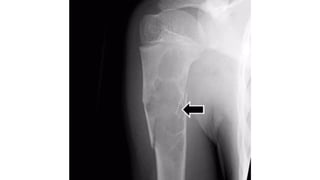

C h o n d r o b l a s t o m a

• R a r e

• • Characteristically occur in epiphyses of apophyses

• of long bones in young patients

• Age

• • < 2 o y r s

• Sex prevalence

• • Slight male predominant

• • L o c a t i o n

• • Most tumors occur in epiphyses of long bones, specially around

• the hips, knees or shoulders

• • Also occur in apophyses

• Well-defined oval lucent lesion

• • S i z e = 1-10 c m

• Position- eccentric in the epiphyses

• Margin- thin sclerotic rim

• • Cortical expansion = +-

• Periosteal r e a c t i o n = +-

• Internal calcification = about quarter of cases = stippled calcification

Plain radiograph and CT Scan features

• Ideal for evaluating transphyseal or transcortical

• expansion

• • To see bone marrow & soft tissue edema

• •Bone s c a n

• • Increased activity in blood-pool phase

• Differentials

• • Osteomyelitis - Brodie's abscess (same location)

• • Giant cell tumor - older age group

MRI